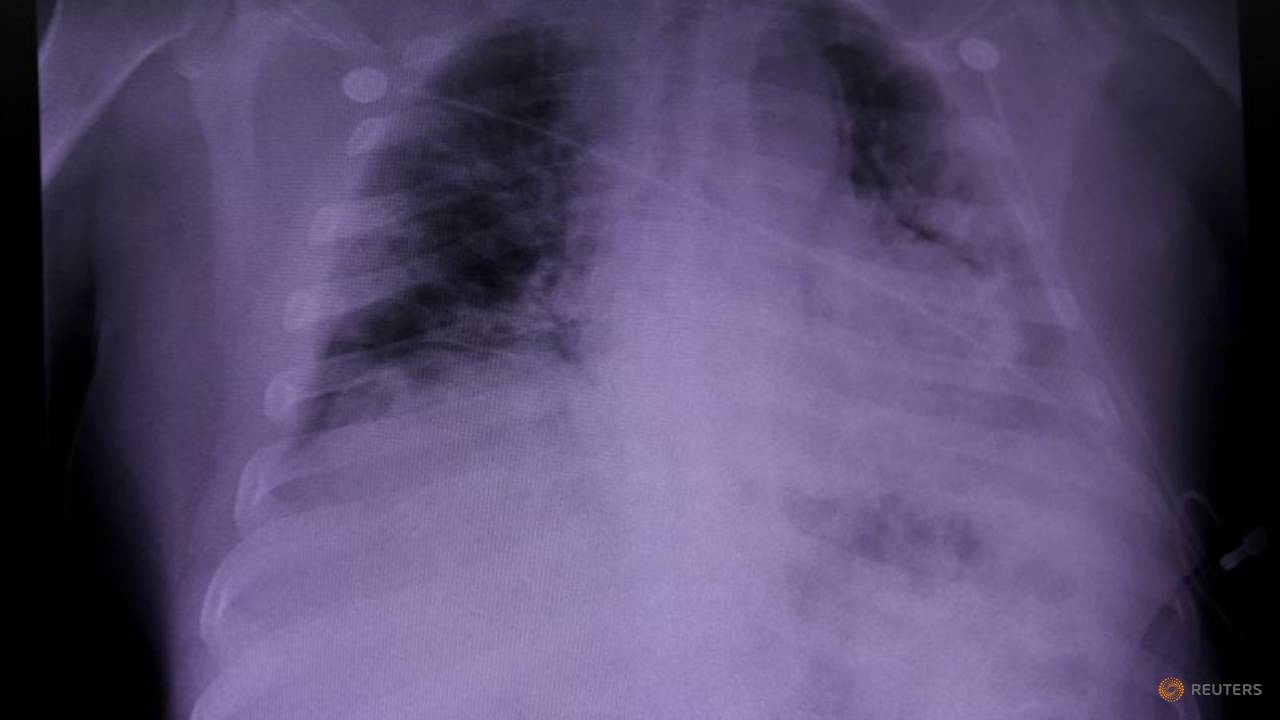

محققان انگلیسی می‌گویند به طور میانگین اگر فردی علائم کرونا را بیشتر از یک دوره ۱۵ روزه نشان دهد، به کرونای بلند مدت مبتلا شده است. دانشمندان کالج سلطنتی لندن برای پی بردن به دلیل وقوع کرونا بلند مدت اقدام به بررسی ریه‌های بیماران کردند. شواهد نشان داد بافت ریه‌های این افراد به شدت در مقابل کرونا آسیب دیده است که همین امر می‌تواند ریشه عوارض بلند مدت بیماری در فرد باشد.

محققان می‌گویند دلیل علائم بلند مدت کرونا در فرد را باید در ویژگی‌های خاص کووید ۱۹ جستجو کرد. شواهد نشان می‌دهد ویروس کرونا یک بیماری ساده نیست که تنها باعث مرگ سلول‌های آلوده شود، بلکه سلول‌های آسیب دیده از کووید ۱۹ در یک بازه طولانی در ریه‌ها باقی می‌مانند، و در نتیجه کرونای بلند مدت در فرد بروز می‌کند.

دانشمندان ایتالیایی برای مشاهده شدت آسیب ویروس کرونا به بافت‌های بدن بیماران اقدام به نمونه گیری از قلب، ریه ها، کبد و کلیه ۴۱ قربانی کرونا از ماه فوریه تا آوریل کردند. بررسی‌ها نشان داد یکی از دلایل وقوع کرونای بلند مدت در بیماران، آسیب گسترده و مخربی بوده که این ویروس به ریه‌های افراد وارد کرده است. حتی اگر فرد از کرونا جان سالم به در ببرد، عوارض آسیب‌های شدید ریوی همچنان در بدن فرد باقی خواهد ماند.

آسیب شدید کرونا بر ریه ها

دانشمندان استرالیایی در تحقیقات خود بیمارانی که به کرونای شدید مبتلا شده و در بیمارستان بستری بودند را مورد مطالعه قرار دادند. شواهد نشان داد ۶ هفته پس از مرخص شدن این بیماران از بیمارستان، بیش از ۸۸ درصد از آن‌ها هنوز علائم آسیب ریوی را داشته‌اند. آزمایشات و سی‌تی اسکن این افراد نشان داد ریه‌های آن‌ها هنوز هم درگیر عوارض ابتلا به ویروس کرونا بوده است.

همچنین ۴۷ درصد این بیماران با گذشت بیش از ۶ هفته از بهبودی از مشکلات تنفسی و ناتوانی در دم و بازدم شکایت داشتند. تحقیقات دانشمندان پس از گذشت ۱۲ هفته (تقریبا ۳ ماه) نشان داد ریه‌های ۵۶ درصد از بهبود یافتگان هنوز هم از عوارض کرونا آسیب دیده است و ۳۹ درصد آن‌ها همچنان مشکل تنفسی دارند.